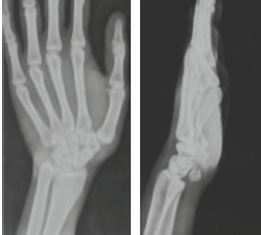

Flexor Carpi Radialis Tendon Stabilization for Chronic First Carpometacarpal Joint Instability: Clinical Outcomes from a Case Report